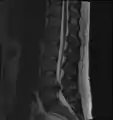

- Magnetic resonance imaging is the gold standard study for confirming a suspected LDH. With a diagnostic accuracy of 97%, it is the most sensitive study to visualize a herniated disc due to its significant ability in soft tissue visualization. MRI also has higher inter-observer reliability than other imaging modalities. It suggests disc herniation when it shows an increased T2-weighted signal at the posterior 10% of the disc. Degenerative disc diseases have shown a correlation with Modic type 1 changes. When evaluating for postoperative lumbar radiculopathies, the recommendation is that the MRI is performed with contrast unless otherwise contraindicated. MRI is more effective than CT in distinguishing inflammatory, malignant, or inflammatory etiologies of LDH. It is indicated relatively early in the course of evaluation (<8 weeks) when the patient presents with relative indications like significant pain, neurological motor deficits, and cauda equina syndrome. Diffusion tensor imaging is a type of MRI sequence used for detecting microstructural changes in the nerve root. It may be beneficial in understanding the changes that occur after herniated lumbar disc compresses a nerve root, and might help in differentiating the patients that need surgical intervention. In patients with a high suspicion of radiculopathy due to lumbar disc herniation, yet the MRI is equivocal or negative, nerve conduction studies are indicated.[44] T2-weighted images allow for clear visualization of protruded disc material in the spinal canal.

MRI scan of cervical disc herniation between C5 and C6 vertebrae

MRI scan of cervical disc herniation between C6 and C7 vertebrae